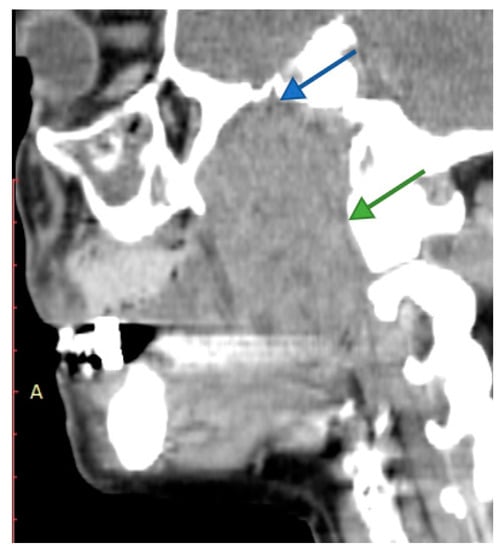

4. Imagery in Extracranial FNSs